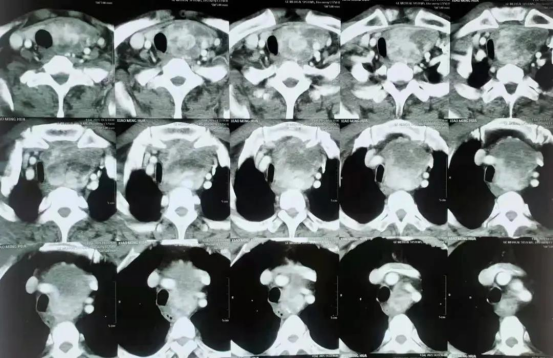

機(jī)緣巧合,張先生在朋友的推薦下來(lái)到臨沂市第三人民醫(yī)院求診,醫(yī)院根據(jù)患者的病情,第一時(shí)間組織了多學(xué)科會(huì)診,外四科聯(lián)合影像科反復(fù)研讀患者病例資料及CT片后認(rèn)為,長(zhǎng)在張先生身上的這個(gè)巨大甲狀腺腫瘤雖然已經(jīng)墜入胸腔,但是憑借他們多年的臨床經(jīng)驗(yàn),認(rèn)為可以不用開(kāi)胸,傳統(tǒng)的頸部切口手術(shù)也能把腫瘤切除。

7月27日,外四科團(tuán)隊(duì)按照術(shù)前制定的手術(shù)方案,在麻醉科、手術(shù)室的鼎力配合下,憑著對(duì)頸部、胸部熟悉的解剖,精湛的手術(shù)技巧和密切的配合,最終將腫瘤與周圍的器官、血管一點(diǎn)點(diǎn)分離開(kāi),完整地從頸部切口將巨大的腫瘤組織拖出,術(shù)后病理為良性腫瘤。術(shù)后恢復(fù)良好,已于昨日出院回家。